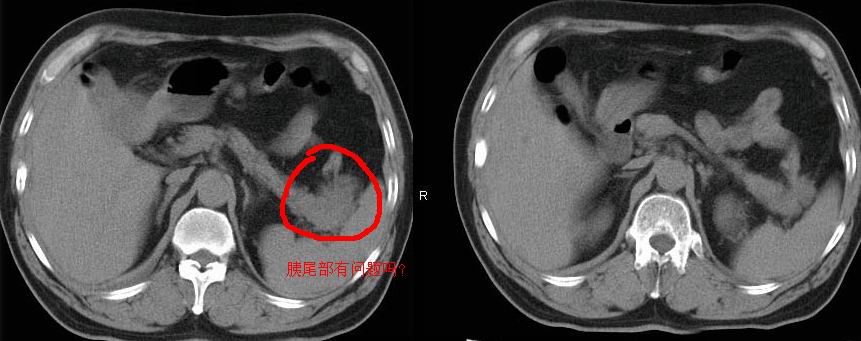

肝内多发转移瘤,右下肺炎症并少量胸水。胃壁增厚建议胃镜,胰尾部“病变”为肠管。

胰尾占位?结肠脾曲?

外院mr结果:胰尾恶性占位。